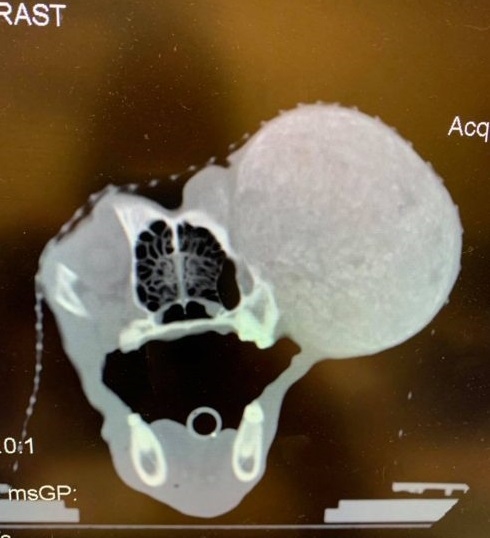

Living on the streets had taken a toll, manifesting as a malignant growth near one of his eyes.

He underwent radiation therapy and battled heartworm disease, yet maintained a lovable and gentle disposition that captivated everyone he met. His story resonated deeply, touching the hearts of many.